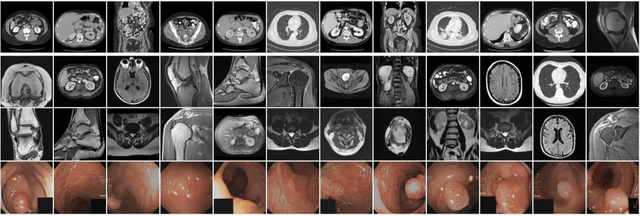

Abstract:Deep learning in medical imaging often requires large-scale, high-quality data or initiation with suitably pre-trained weights. However, medical datasets are limited by data availability, domain-specific knowledge, and privacy concerns, and the creation of large and diverse radiologic databases like RadImageNet is highly resource-intensive. To address these limitations, we introduce RadImageGAN, the first multi-modal radiologic data generator, which was developed by training StyleGAN-XL on the real RadImageNet dataset of 102,774 patients. RadImageGAN can generate high-resolution synthetic medical imaging datasets across 12 anatomical regions and 130 pathological classes in 3 modalities. Furthermore, we demonstrate that RadImageGAN generators can be utilized with BigDatasetGAN to generate multi-class pixel-wise annotated paired synthetic images and masks for diverse downstream segmentation tasks with minimal manual annotation. We showed that using synthetic auto-labeled data from RadImageGAN can significantly improve performance on four diverse downstream segmentation datasets by augmenting real training data and/or developing pre-trained weights for fine-tuning. This shows that RadImageGAN combined with BigDatasetGAN can improve model performance and address data scarcity while reducing the resources needed for annotations for segmentation tasks.